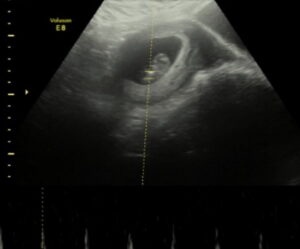

I am 11 weeks as of yesterday (3/16) with tubal reversal baby #2.

My genetic testing results have come back and we are having our first little boy!!